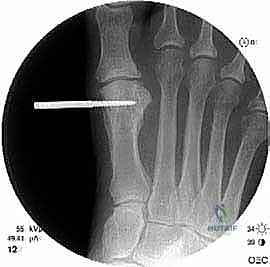

الخطوة الرابعة: الإطالة والطعوم العظمية (Bone Grafting)

يتم إبعاد طرفي العظم المقصوص بلطف للوصول إلى الطول التشريحي المطلوب (والذي تم حسابه مسبقاً في صور الأشعة). لملء الفراغ الناتج عن الإطالة، يتم استخدام طعم عظمي (Bone Graft).

* الطعم الذاتي (Autograft): غالباً ما يتم أخذ قطعة صغيرة من العظم من كعب المريض (عظم العقب) أو من عظم الحوض، وهو الخيار الأفضل لأنه يحفز الالتئام السريع.

* الطعم الصناعي أو العظم البنكي (Allograft): يمكن استخدامه في بعض الحالات لتجنب إحداث جرح إضافي.